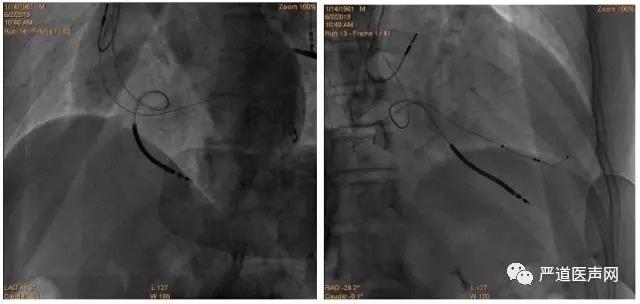

首先进行冠状静脉球囊造影,显示血管较细,预计导线通过困难,考虑可能近段有侧枝或血管未显示,于是在无球囊的情况下再次造影,未发现合适血管。决定尝试近段血管,导丝顺利通过, 但由于靶静脉狭窄,反复尝试电极无法进入,随后深插鞘管以增加支撑力,导丝进入较高分支,电极仍无法进入。于是尝试前侧血管,导丝通过后,电极仍然无法通过。重新分析造影后,尝试后静脉或心中静脉血管, 回撤鞘管至窦口处,保留原PTCA导丝作为支撑,使用另一根PTCA导丝探入心中静脉,尝试送入电极,由于靶静脉开口处扭曲电极依然无法进入。随后使用鞘中鞘在侧枝开口作为支撑,在鞘中鞘支撑下左室电极进入靶静脉, 尝试把电极往深处送,测试左室导线参数良好,阈值Tip端阈值1.5V/0.4ms,5V无膈神经刺激。最后植入右房、右室电极。

AP

LAO 30°

RAO 30°

术后最终影像

如果心中静脉有理想的左侧侧支,可以作为左室导线的靶静脉。使用鞘中鞘有助于顺利植入导线。